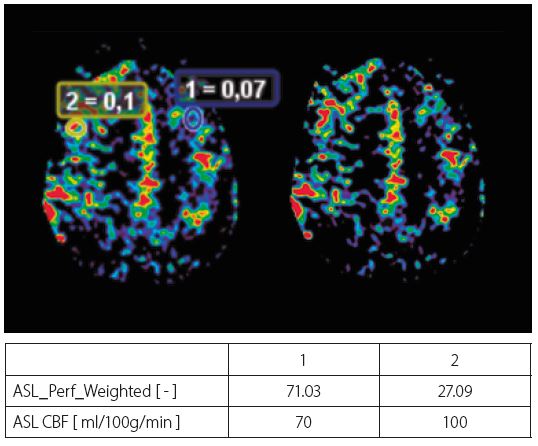

У таблиці на рисунку 3 показано значення церебрального кровотоку як для нормальної зони, так і для склерозу: виявлено зниження на 25% церебрального кровотоку для склерозу, що можна пояснити низькою васкуляризацією цієї області.

Рис. 3. Показано оптичні тракти, накладені на аксіальний MPR FLAIR. У таблиці наведені абсолютні значення церебрального кровотоку (CBF) в нормі та в зоні склерозу.

Рис. 5. Карти перфузії ASL з областями інтересу, розміщеними в патологічних і контрольних областях. У таблиці показано значення церебрального кровотоку (CBF), які відрізняються між лівим і правим зображенням.